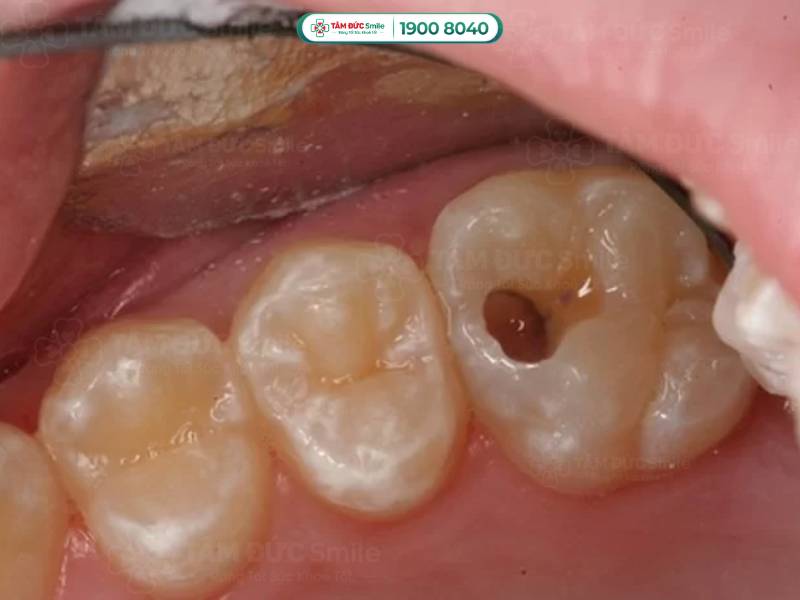

1.2. Uống nước đá bị ê răng do răng bị sâu

Bất kỳ ai và bất kỳ độ tuổi nào cũng có thể bị sâu răng. Đây là bệnh lý răng miệng phổ biến, nếu bạn vệ sinh răng miệng không đúng cách sẽ có nguy cơ cao mắc phải.

Sâu răng được chia thành 4 cấp độ, trong đó, sâu răng độ 1 và 2 là cấp độ nhẹ nhất, vi khuẩn chưa đi sâu vào tủy răng. Bị sâu răng độ 3 và 4 là mức độ nghiêm trọng hơn, vi khuẩn đã lan sâu vào bên trong răng, gây viêm nhiễm hoặc hoại tử tủy răng. Lúc này, bạn thường xuyên phải đối mặt với cảm giác đau nhức, ê buốt ở răng. Cơn đau sẽ nặng hơn khi bạn ăn thực phẩm nóng, uống nước đá, hoặc thậm chí là súc miệng bằng nước lạnh,...

Tỷ lệ bị sâu răng ở trẻ em cao hơn so với người lớn. Vì trẻ có thường ăn nhiều đồ ngọt và chưa thực sự ý thức về tầm quan trọng của việc làm sạch răng. Nếu trẻ uống nước đá bị ê răng, bạn có thể suy đoán ngay là do răng trẻ bị sâu, sau đó đưa trẻ đến nha khoa để điều trị.

Sâu răng là bệnh lý răng miệng phổ biến